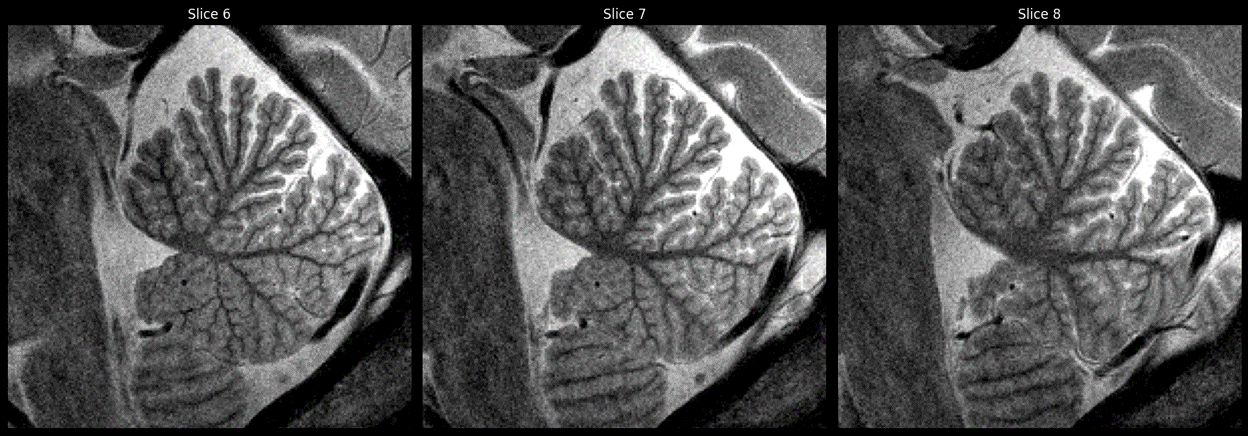

Cervelets_7T_enfants.pngCervelets d'enfant de 6 ans obtenus avec un IRM à 7T © CEA/NeuroSpin

« C’est une première mondiale à ce niveau de technicité des images et de garantie de sécurité. L’IRM 7T nous permet de voir ce que le 3T ne montre pas : les détails fins du cerveau, la vascularisation, le métabolisme cérébral… et son activité à l’échelle individuelle. C’est un apport majeur pour l’étude et la compréhension des troubles du neurodéveloppement et des maladies du cerveau de l’enfant, comme par exemple ceux causés par l’alcoolisation fœtale. Chez les enfants concernés, très affectés dans leur fonctionnement cognitif et dont le cervelet est trop petit, nous avons montré que les régions du cervelet les plus atteintes étaient des régions plutôt impliquées dans le fonctionnement moteur… Aujourd’hui, l’IRM à 3T ne nous permet pas d’explorer efficacement ce paradoxe neurodéveloppemental, alors nous nous tournons vers le 7T pour avancer »

Dr David Germanaud, neuropédiatre à l’Institut Robert-Debré du Cerveau de l'Enfant et chercheur au CEA à NeuroSpin.

​Installée depuis 2007 à NeuroSpin au CEA Paris-Saclay, l’IRM 7 teslas (puissance du champ magnétique de la machine), est un outil d’imagerie de pointe parmi les plus avancés au monde. Jusqu’ici réservée aux adultes, la technologie a nécessité un long travail de recherche, de développement et de validation réglementaire pour être utilisée chez l’enfant. Cet effort d’innovation vise à mieux comprendre le neurodéveloppement, notamment ses variations typiques et pathologiques. L’IRM 7T permet en effet une meilleure résolution des images et des contrastes accrus, donnant accès à des détails invisibles aux champs magnétiques plus faibles jusque-là disponibles (1,5 ou 3T). Il permet de voir par exemple des anomalies de la structure fine du cervelet ou des lésions à l’intérieur même du cortex, des variations individuelles de l’activité cérébrale ou des anomalies du métabolisme.